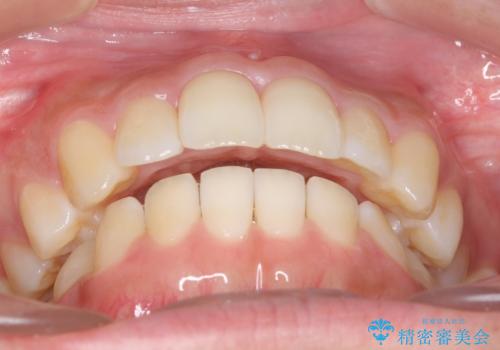

受け口、すきっ歯を インビザラインで モニター治療

- 前歯のすき間と受け口を気にして来院。

マウスピースでしっかり閉じています。

下の前歯を後方に移動するため、ゴムを上下のマウスピースにかけてもらいました。